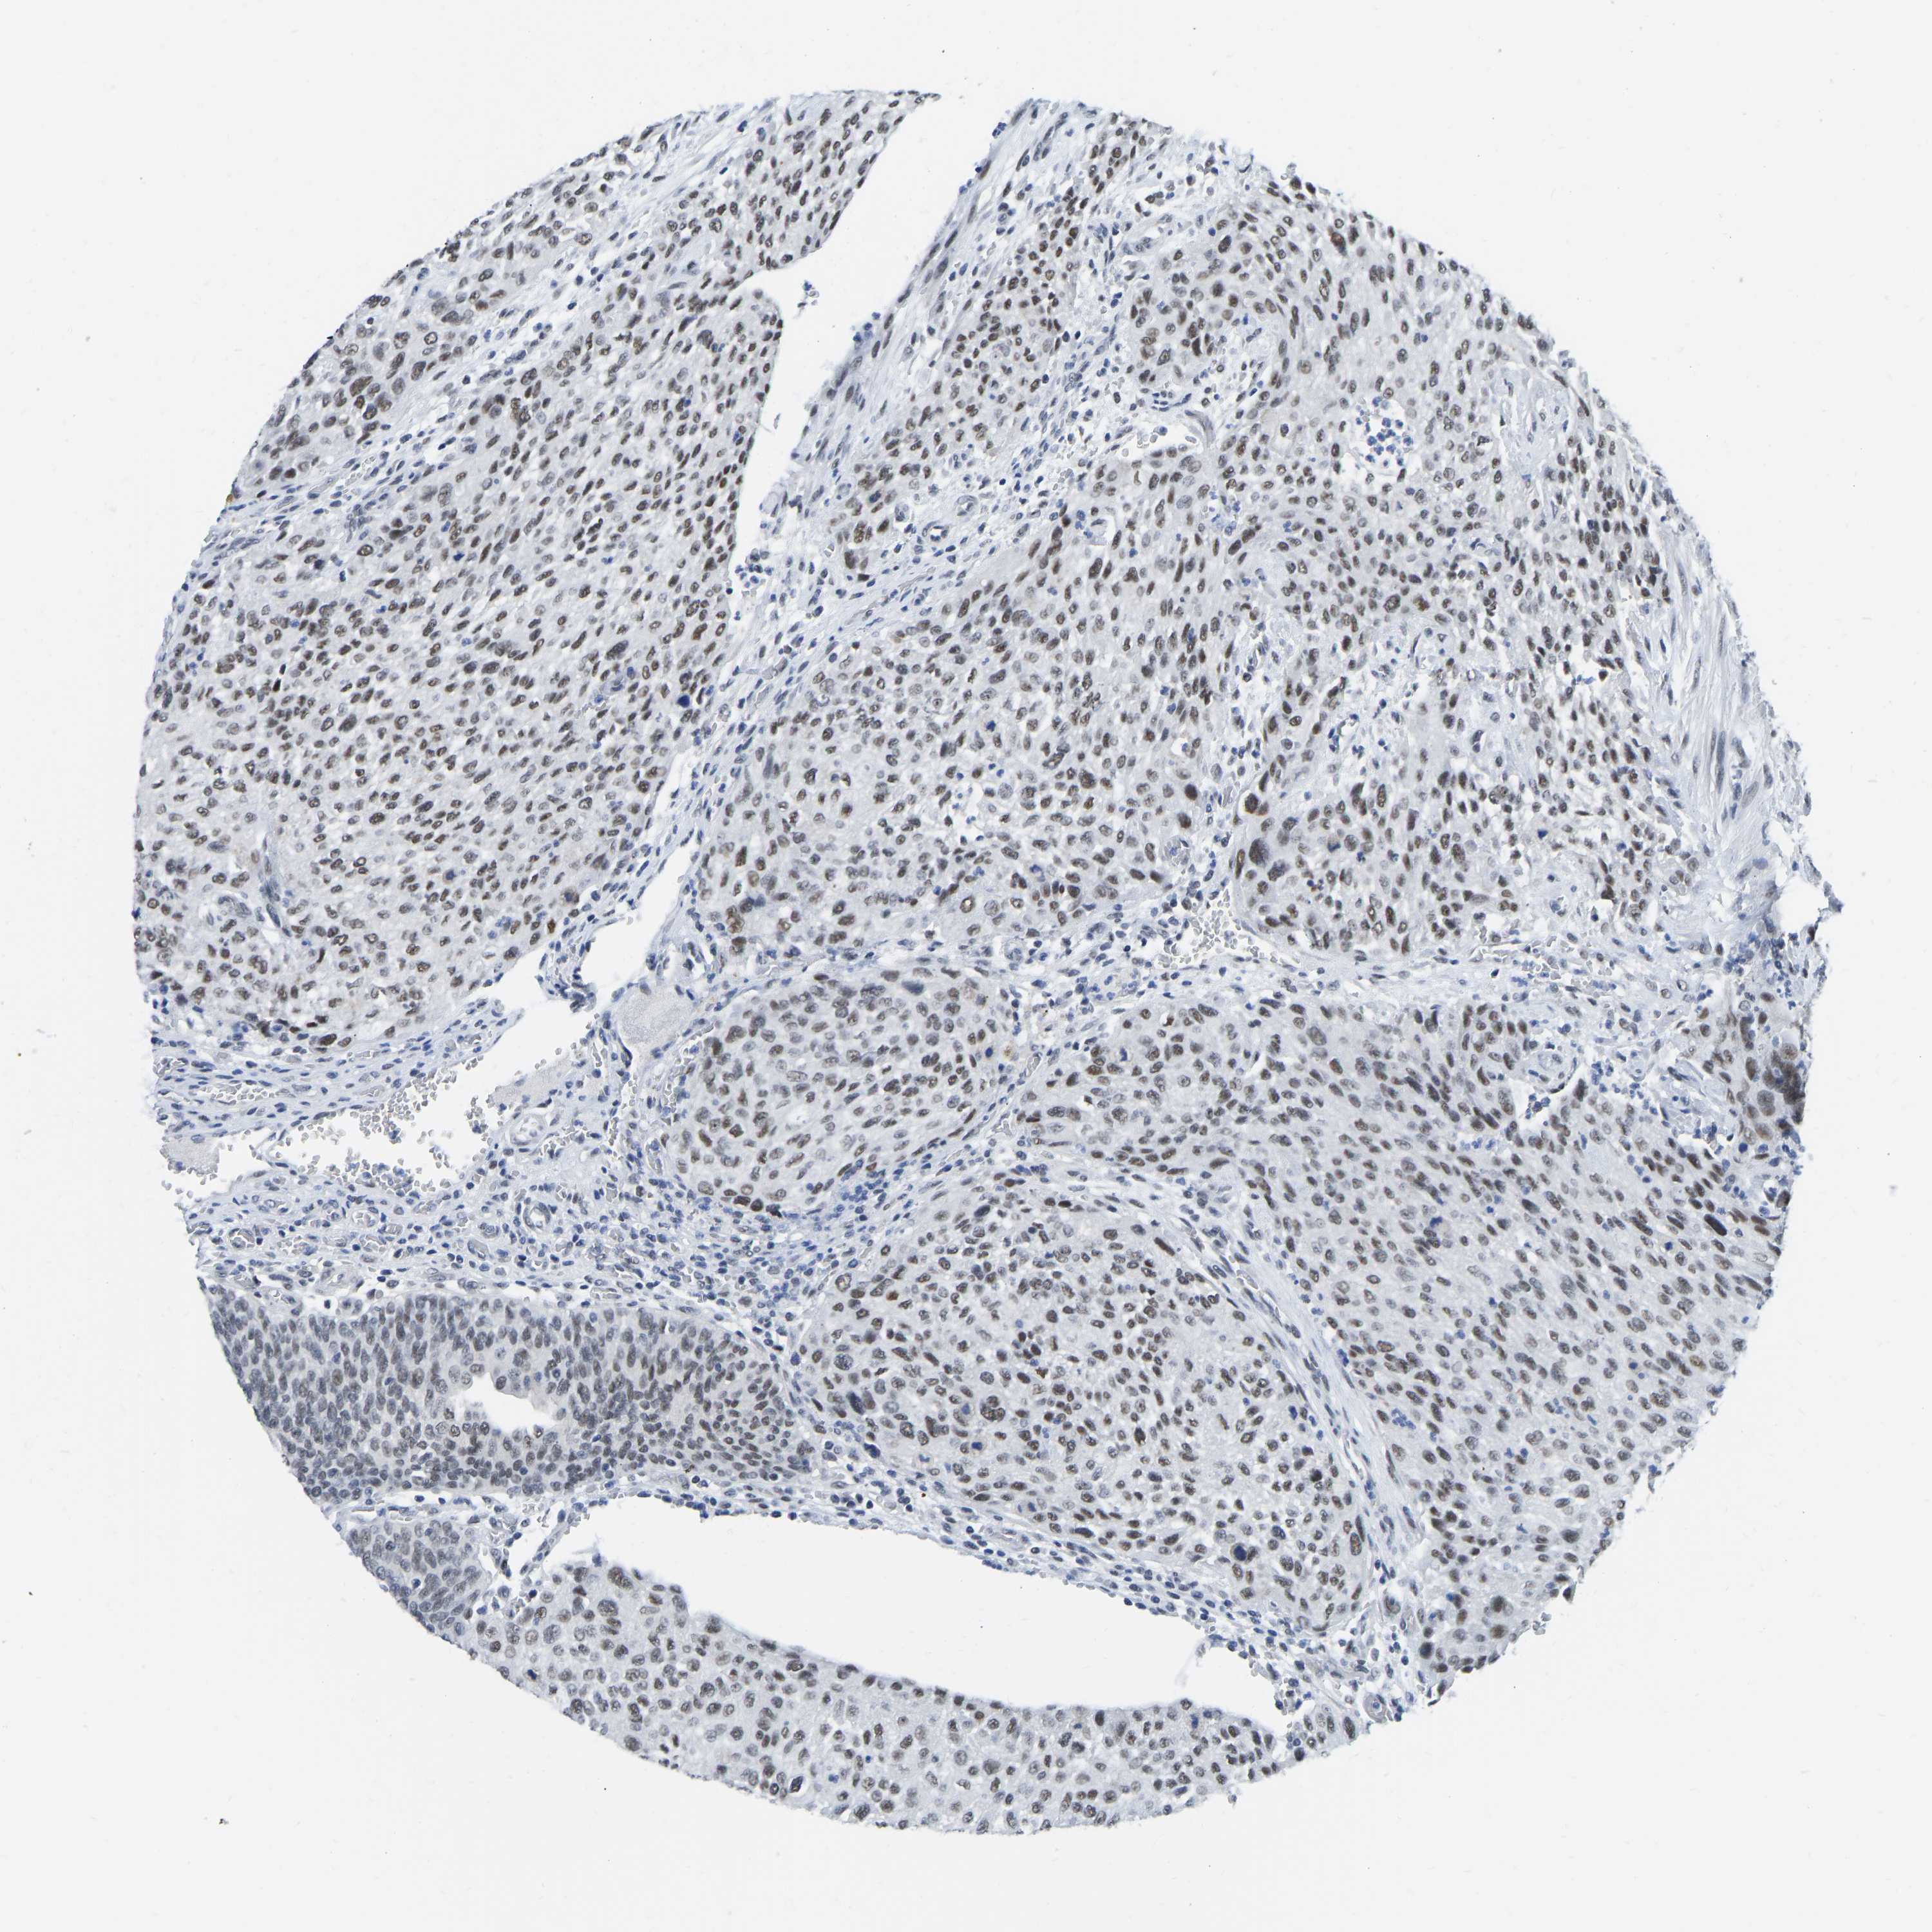

UROTHELIAL CANCER - Protein expressioni

A mouse-over function shows sample information and annotation data. Click on an image to view it in a full screen mode. Samples can be filtered based on level of antibody staining by selecting one or several of the following categories: high, medium, low and not detected. The assay and annotation is described here.

Antibody stainingi

Antibody staining in the annotated cell types in the current human tissue is reported as not detected, low, medium, or high, based on conventional immunohistochemistry profiling in selected tissues. This score is based on the combination of the staining intensity and fraction of stained cells.

Each image is clickable and will lead to virtual microscopy that enables deeper exploration of all samples and also displays staining intensity scores, fraction scores and subcellular localization as well as patient and tissue information for each sample.

Antibody CAB019416

Staining

High

Medium

Low

Not detected

Intensity

Strong

Moderate

Weak

Negative

Quantity

>75%

75%-25%

<25%

None

Location

Nuclear

Cytoplasmic/membranous

Cytoplasmic/membranous,nuclear

Urothelial carcinoma, Low grade

Urothelial carcinoma, High grade